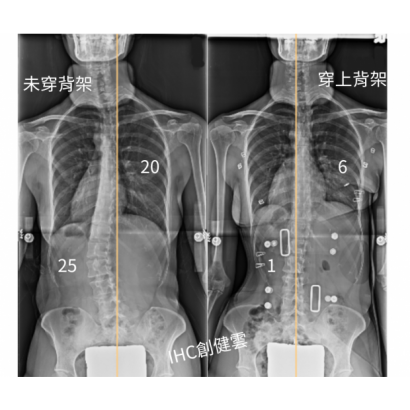

33歲脊椎側彎成年女性,胸彎20度,腰彎25度 穿上背架後立即矯正效果優異

33歲脊椎側彎女性,胸彎20度,腰彎25度,

穿上【施羅斯側彎矯治背架】後,胸彎6度,腰彎1度。

背架的立即矯正效果對成年人來說非常不錯~